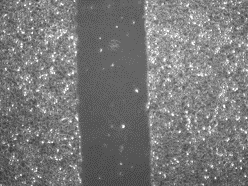

Xác minh sơ bộ PIXCELL BIOM™

Kết quả được chứng minh trong phòng thí nghiệm là nhanh hơn 56% so với lipid da trung bình *

* Kiểm tra xem độ dài ở giữa hẹp đến mức nào.

- Trước khi sử dụng chất thử nghiệm

- 12 giờ sau khi dùng chất thử

Sau khi dùng chất thử nghiệm cho đối tượng thử nghiệm nhận được kích thích trung tâm và quan sát trong 12 giờ, tỷ lệ thay đổi 75,8% đã được xác nhận

ở đối tượng thử nghiệm được dùng PixelBiome™ .